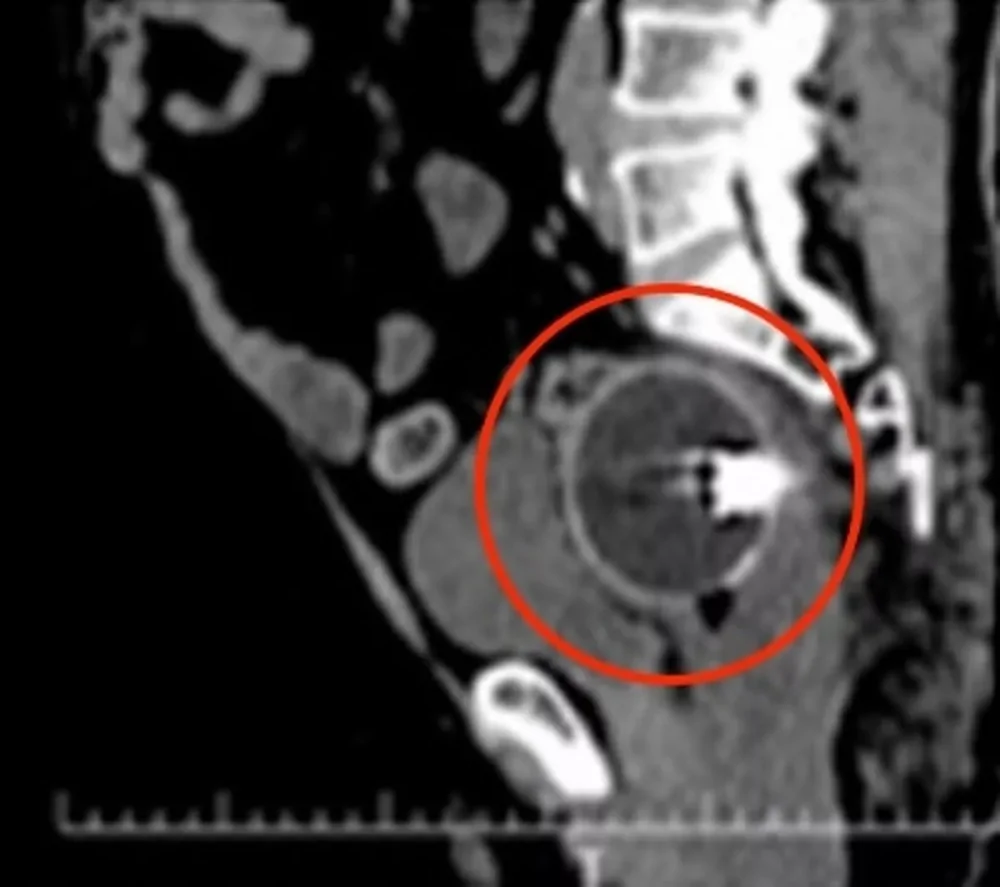

Врачи убедились, что в прямой кишке пациента, примерно в 7 сантиметрах от его заднего прохода, застрял круглый инородный предмет диаметром около 6,5 сантиметров. Это была прозрачная сфера, частично наполненная красной жидкостью, на боках которой красовались мультяшные личики.

Чтобы извлечь шарик, хирурги придумали хитроумный план, максимально облегчающий их работу. Они поместили пациента под общий наркоз, а затем с помощью скальпеля проткнули эластичный шарик. Вся жидкость из шарика вытекла, а общий размер игрушки уменьшился из-за выхода воздуха. Затем шар был успешно удален с помощью щипцов и специального зажима через прямую кишку мужчины.